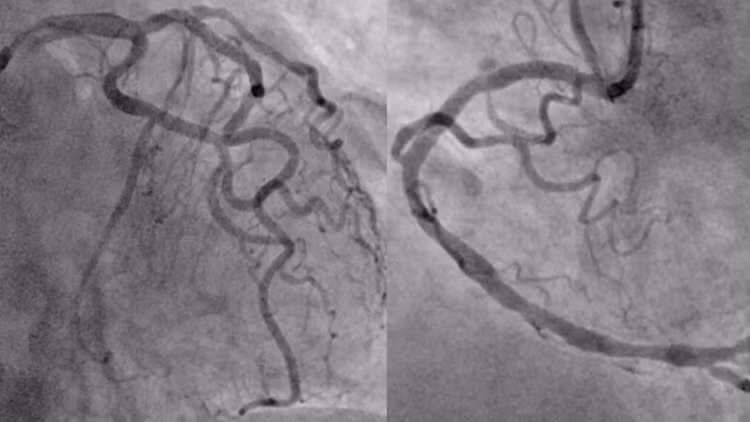

Người bệnh sau đó được đưa đến phòng DSA để được chụp động mạch vành cấp cứu. Kết quả chụp mạch vành cho thấy tắc hoàn toàn động mạch mũ, hẹp nặng động mạch liên thất trước và vành phải.

Sau khi giải thích kỹ chẩn đoán, định hướng điều trị, các lợi ích và nguy cơ của thủ thuật cho người nhà, người bệnh lần lượt được can thiệp nong bóng và đặt stent thành công cả ba nhánh động mạch mũ, động mạch liên thất trước và động mạch vành phải. Người bệnh sau đó được chuyển lên khoa Hồi sức tích cực – Chống độc để tiếp tục điều trị.

Hình ảnh mạch vành của người bệnh sau khi được can thiệp tái thông toàn bộ các động mạch vành tắc và hẹp. Ảnh BV

Hình ảnh chụp động mạch vành cho thấy tắc hoàn toàn động mạch mũ (mũi tên đỏ), hẹp nặng cả động mạch liên thất trước (mũi tên vàng) và động mạch vành phải (mũi tên xanh).